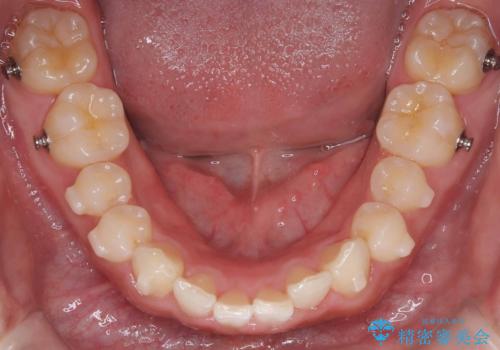

歯を抜かずに叢生(デコボコ歯列)と過蓋咬合を改善する事が出来ました。

インビザラインによる治療でも十分に美しい歯並びを実現でき、患者様にも大変ご満足いただけました。